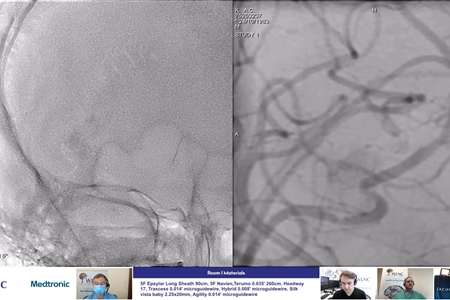

WLNC LIVE & WARM-UP CASES

WLNC 2020 - SECOND DAY

WLNC 2020